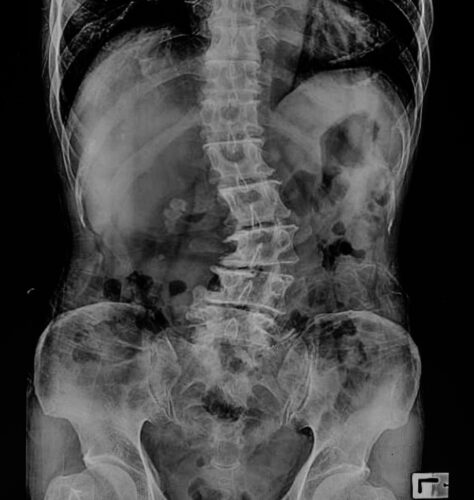

ما طرق التشخيص؟

يبدأ التشخيص عادةً بـ:

فحص سريري شامل لتقييم شكل العمود الفقري والحركة

أشعة سينية لتحديد درجة الانحناء

تصوير بالرنين المغناطيسي إذا كان هناك ضغط على الأعصاب